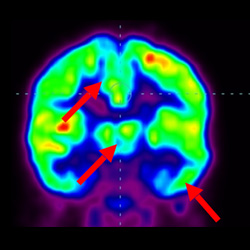

干細胞治療腦癱后改善的客觀放射學證據

細胞治療后,藍色和黑色區域減少,并且看到更活躍的區域。這表明損傷減少并改善了大腦功能。

細胞治療前 PET CT 掃描顯示神經組織中的藍/黑色區域,表明腦癱引起的大腦損傷。

這證明細胞療法是治療腦癱兒童安全有效的方法。細胞療法可以更新大腦損傷的核心,并且可以通過 PET CT 掃描來監測大腦的改善情況。這些細胞療法與標準治療一起促進腦癱兒童的生長和改善。